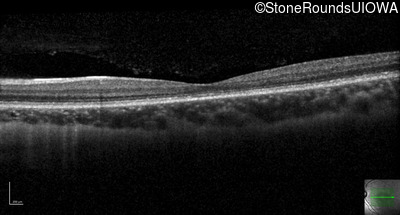

Optical Coherence Tomography - Right - 20/32 -2 sc

Exemplar / OCT Stack

OCT Stack